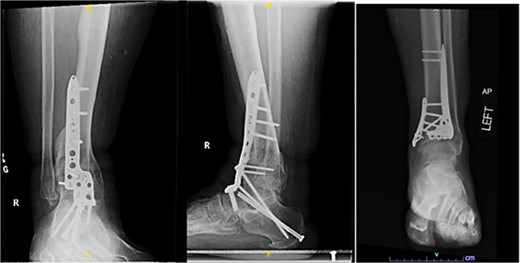

Outcome

One year after the initial surgery, the left leg healed without any complications. However, the right leg developed nonunion through the distal tibia, along with posttraumatic arthritis. As a result, the patient underwent a right ankle fusion. Additionally, 2.5 years after the index surgery (1.5 years after the ankle fusion), the patient required removal of the right lateral fibular plate due to painful hardware. Six months later (3 years post-index surgery), the patient then underwent subtalar fusion due to post-traumatic arthropathy and ongoing pain (Fig. 2).

Radiographs of patient 1 obtained 3 years after the index procedure, including AP view of the left ankle and lateral and oblique views of the right ankle following subtalar fusion.